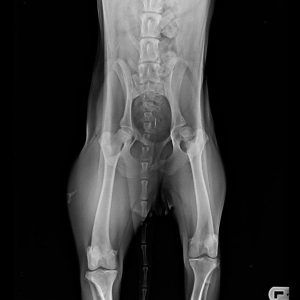

Füli kutyusunk egy jelenleg kb másfél éves, mentett, bántalmazott keverék, szuka kutyus (15 kg-os, vékony testalkatú, közepes magasságú, rövidszőrű keverék kutyus). Sérülése egy korábbi bántalmazásból eredt, mikor kiskutyaként husánggal úgy megverhették, hogy combnyaktörése lett. Ezt mi derítettük ki, mikor hozzánk került tavaly októberben. Akkor észrevettük, hogy aggasztóan sántít, és elvittük megröntgeneztetni. Több orvos véleményét is kikértem, és mindannyian azt tanácsolták, hogy műttessük meg (elég drasztikus műtéttel, a combcsontfej egy részét kivágták volna).

Molnár doktor úr egyedüliként, a röntgen kép alapján, arra bíztatott, hogy mivel a kutyus még növekedésének vége előtt állt, próbáljunk ki egy 3 hónapos csont- és porcépítő csomagot. Így is tettünk. Már kezdetben is nagy javulást észleltünk. Pár hét után el-elmaradozott a sántítás és szép lassan teljesen elmúlt. De természetesen nem elégedtünk meg ennyivel. Májusban az ivartalanítási műtét során kértem az orvost, hogy készítsen röntgenfelvételt Füli lábáról. A röntgen el is készült, és nagy örömünkre, már ez az állatorvos is azt mondta, hogy nincs szükség a combcsontfej műtétjére.